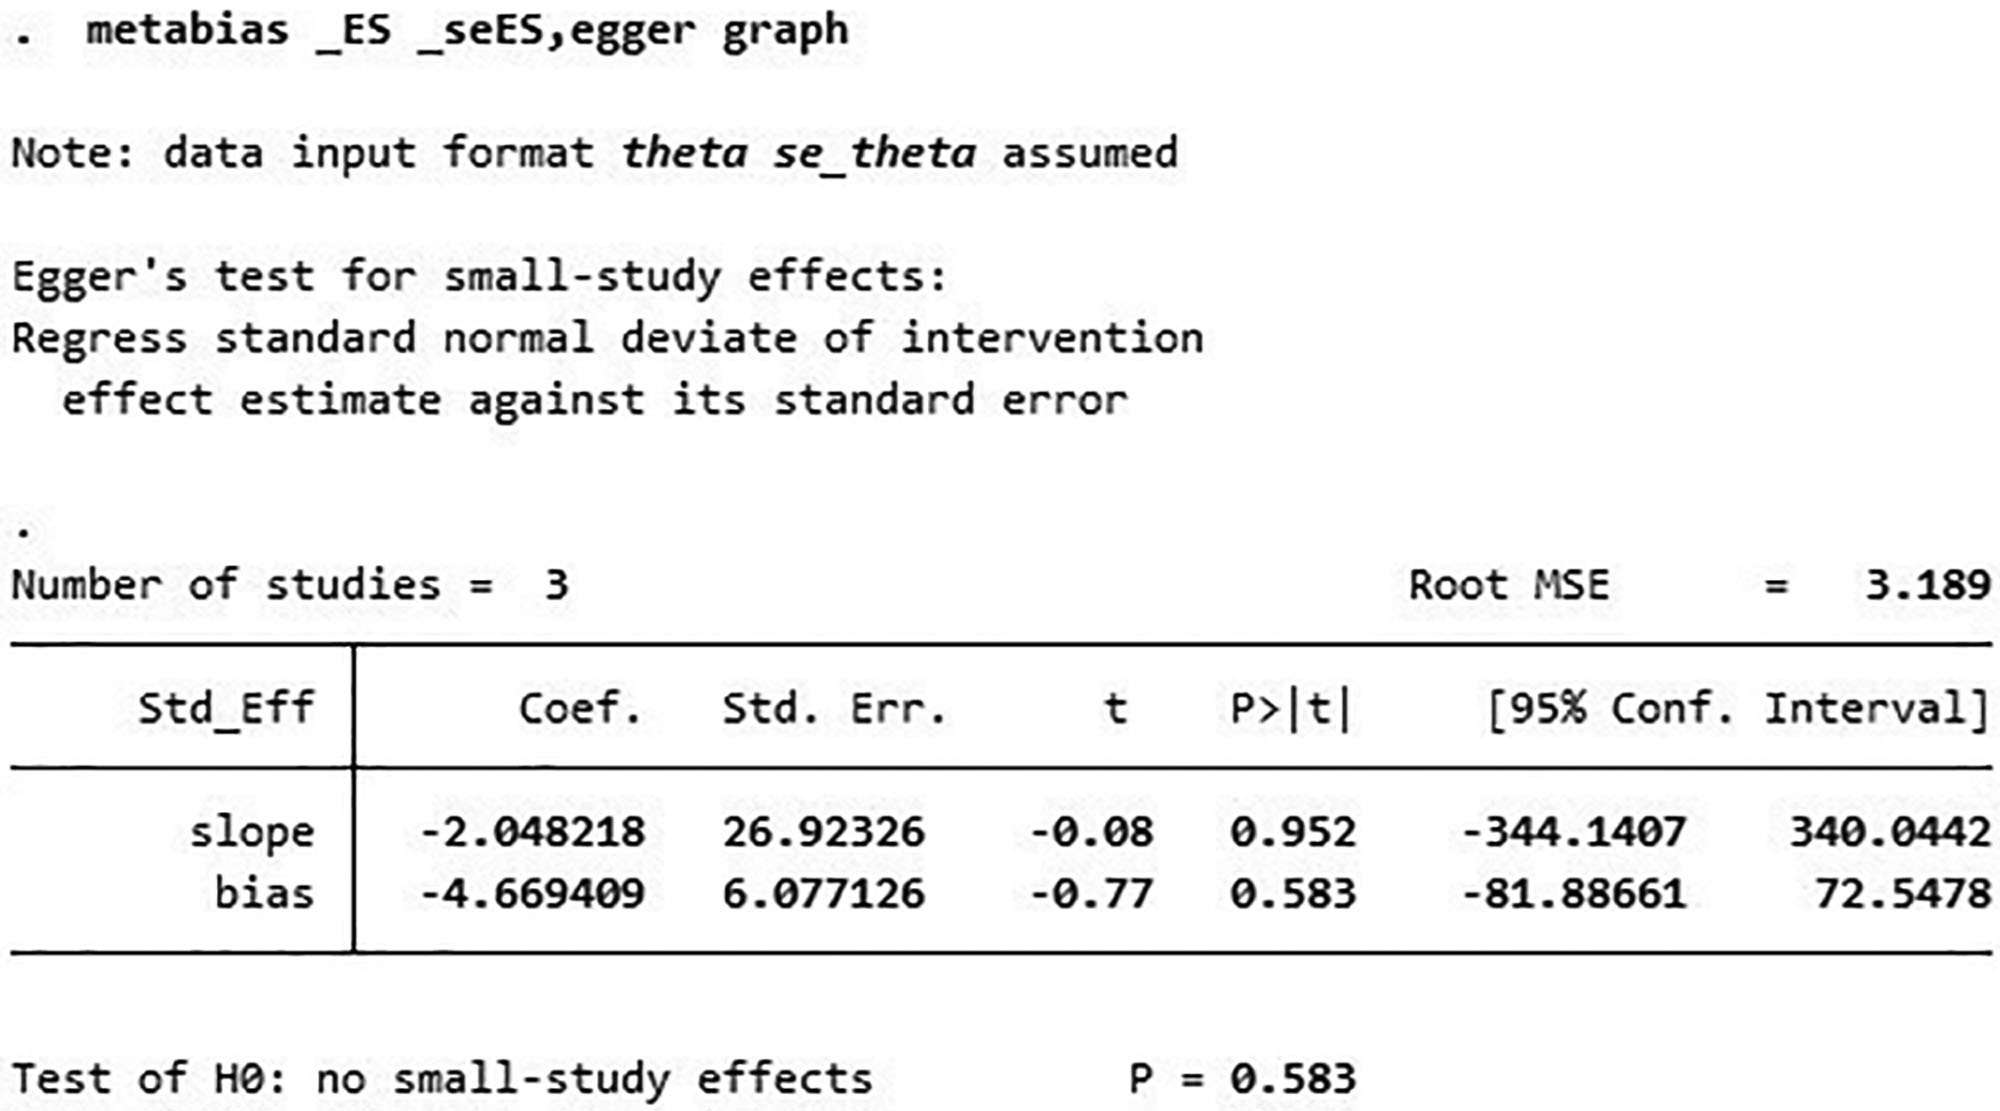

出版偏見:對(duì)納入研究進(jìn)行了發(fā)表偏倚分析,漏斗圖顯示W(wǎng)OMAC不對(duì)稱,而KLS對(duì)稱,提示W(wǎng)OMAC結(jié)果可能存在發(fā)表偏倚(圖4、圖5),因此進(jìn)行了Egger檢驗(yàn),結(jié)果顯示P=0.583,提示不存在發(fā)表偏倚(圖6)。

WOMAC=西安大略和麥克馬斯特大學(xué)骨關(guān)節(jié)炎指數(shù)。

討論:本研究納入3個(gè)試驗(yàn),分析臍帶間充質(zhì)干細(xì)胞治療膝骨關(guān)節(jié)炎的療效。Meta分析顯示,接受臍帶間充質(zhì)干細(xì)胞治療膝骨關(guān)節(jié)炎的患者的WOMAC和KLS均較對(duì)照組有明顯改善,提示臍帶間充質(zhì)干細(xì)胞可以改善膝骨關(guān)節(jié)炎的功能和疼痛。Egger檢驗(yàn)提示無出版偏倚。但WOMAC結(jié)果存在異質(zhì)性,敏感性分析提示結(jié)果穩(wěn)定,因此異質(zhì)性高可能與納入研究數(shù)量少或樣本量不足有關(guān)。